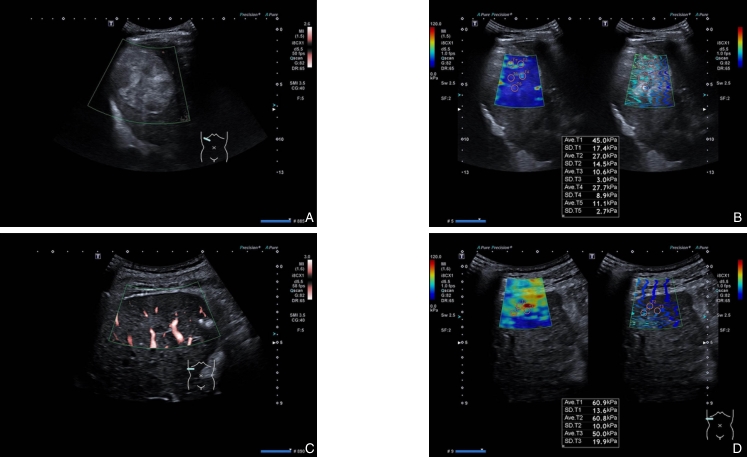

图2 典型无复发与复发病例超声特征 A-B:56岁男性无复发患者,确诊肝硬化肝癌7个月,TACE-RFA序贯治疗术后6个月超声检查显示,肝右叶见6.6 cm×5.6 cm高回声病灶,SMI示病灶内部及边缘无明显血流信号,Emean为24.3 kPa;C-D:62岁男性复发患者,确诊肝硬化肝癌1年,TACE-RFA术后6个月超声检查显示,病灶大小1.8 cm×1.4 cm,边界清、形态不规则、内回声不均,SMI见病灶内线样血流信号,Emean为57.2 kPaFig.2 Representative ultrasound findings in non-recurrent and recurrent cases A-B: A 56-year-old male without recurrence, diagnosed with cirrhosis and liver cancer for 7 months, and 6 months after sequential TACE-RFA, ultrasonography shows a 6.6 cm×5.6 cm hyperechoic lesion in the right hepatic lobe and SMI demonstrates no detectable intralesional or peripheral vascular signals, with the Emean of 24.3 kPa; C-D: A 62-year-old male with recurrence. Diagnosed with cirrhosis and liver cancer for 1 year, and 6 months after TACE-RFA, ultrasonography reveals a 1.8 cm×1.4 cm lesion with well-defined margins, irregular morphology, and heterogeneous echotexture, and SMI demonstrates linear intralesional vascular signals, with the Emean of 57.2 kPa